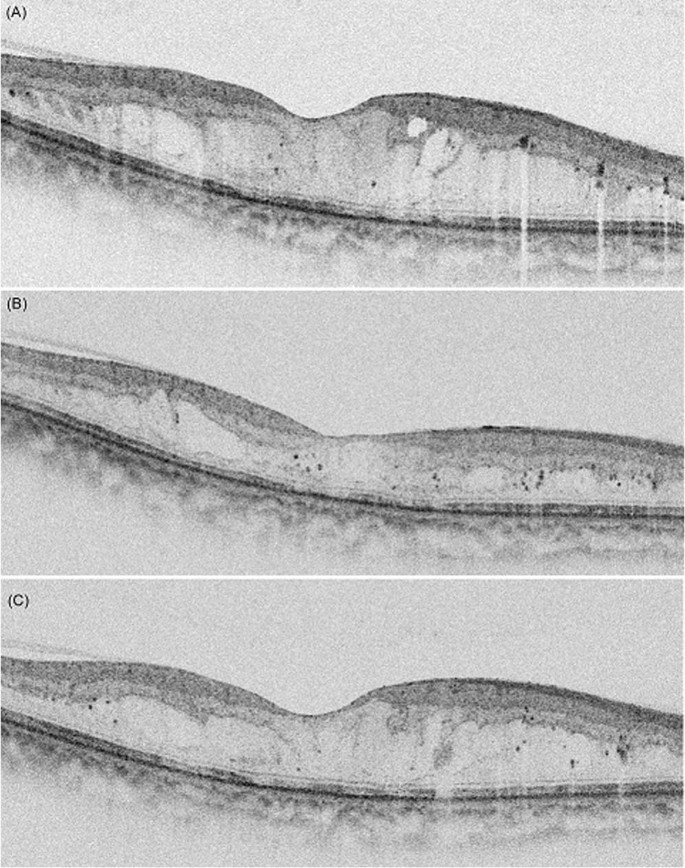

In the multivariate linear regression analyses for identifying factors related to level of CST reduction after treatments in DME, the aqueous interleukin (IL)-10 level showed significant association (β = 37.31, p = 0.018, Table 2). Factors identified as being associated with the interval are summarized in Table 3. In multivariate linear regression analyses including OCT findings and biomarkers of the aqueous humor, the interval was associated with IL-8 levels of the aqueous humor and the number of hyperreflective foci (HF) using OCT (β = -0.016, p = 0.037 and β = −0.073, p = 0.035, respectively). Multivariate logistic regression for identifying factors affecting a short duration (<4 months) of macular stabilization showed that the number of HF (>10) was significantly associated with a shorter duration of action (odds ratio [OR]: 17.17, p = 0.010, Table 4, Fig. 2).

A representative patient who had diabetic macular edema (DME) with multiple hyperreflective foci (HF) and a shorter duration of macular stabilization after dexamethasone implantation. (A) The baseline spectral domain-optical coherence tomography (SD-OCT) image shows center-involving DME with multiple HF. (B) SD-OCT shows that the DME is decreased at 2 months after intravitreal dexamethasone implantation. (C) SD-OCT showing that DME recurred at 3 months after intravitreal dexamethasone implantation.